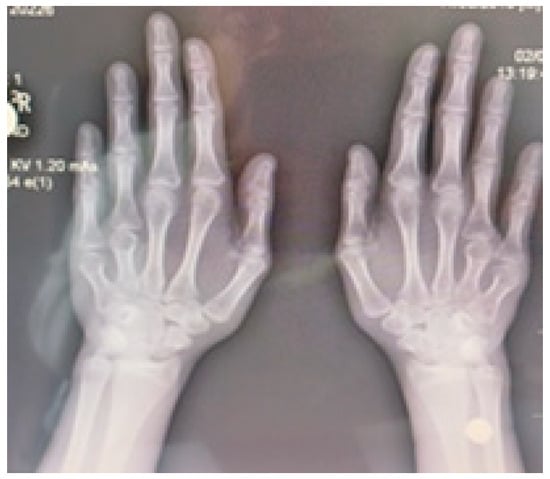

Radiographic examination confirmed bilateral hypoplasia of the metacarpals and phalanges of digits IV and V of the hands (Figure 4), and hypoplasia of the metatarsals and phalanges of digits IV and V of the feet (Figure 5).

Figure 4. Radiograph of both hands demonstrating bilateral hypoplasia of the fourth and fifth metacarpal bones.